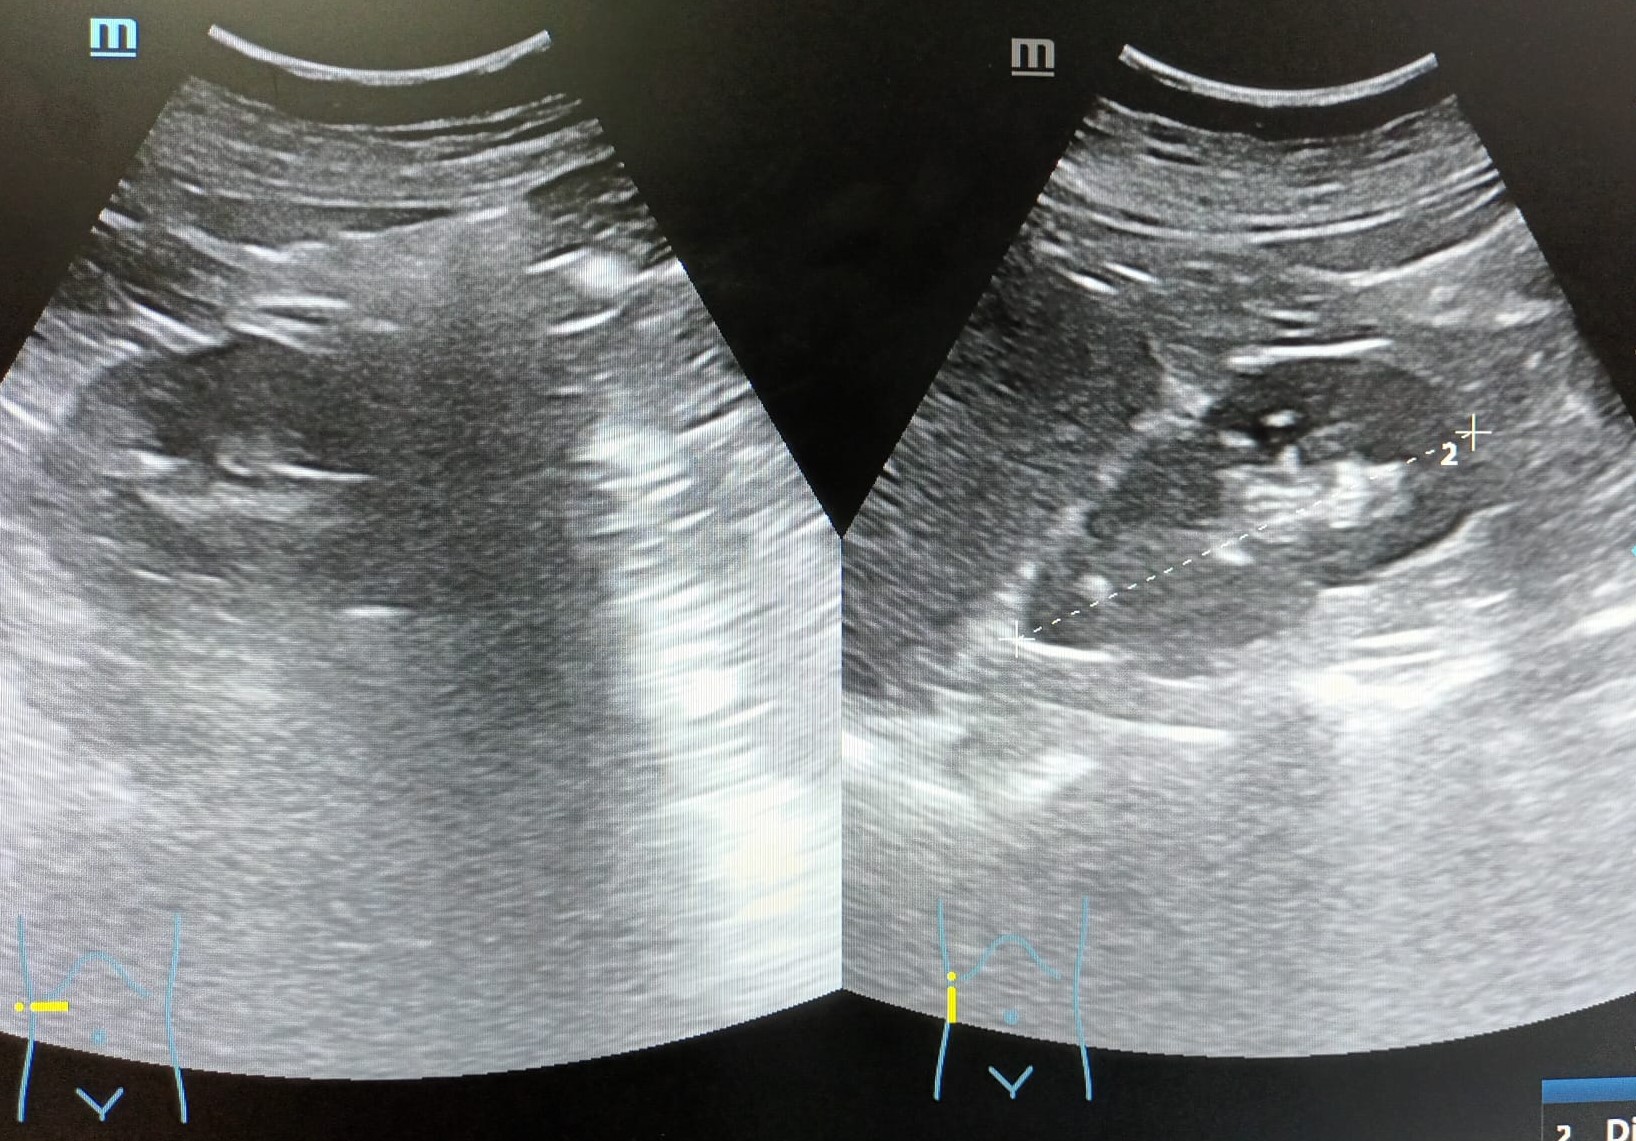

Ambos riñones de tamaño (derecho 99,7 mm e izquierdo 112,6 mm de longitud cráneo-caudal) y localización normal, con buena diferenciación corticomedular, sin lesiones ocupantes de espacio ni imágenes litiásicas en su interior, sin signos de uropatía obstructiva.

Vejiga: lesión hiperecogénica, de bordes bien definidos, adherida a pared, en zona del trígono vesical, colindante con uréter izquierdo, que no capta Doppler, de aproximadamente 4,2 x 6,7 mm.